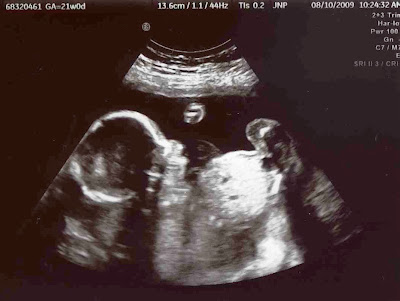

This morning I had my 20 week ultrasound.

I feel HUGE for just over 20 weeks!   (The baby did measure a little big, just over 21 weeks, but still!!  I think I need to start eating more salads and less desserts...  A bit of exercise would probably be a good thing too. )

Hubby met us at the doctors office.  It was so much fun to watch our children "see" their newest sibling for the first time.  Snuggles was so cute and kept pointing to the screen saying "Baby!!"

We were all so happy and relieved that everything still looks just perfect and that this coming Christmas we will be welcoming a...

... beautiful and healthy baby...

... with tiny little arms...

... perfect little feet ...

... who is most definitely a GIRL!!!!

~ A few more pictures of our little "Rose" ~

Yes, that is her little foot next to her face!

In this one it is her hand next to her cute little mouth!